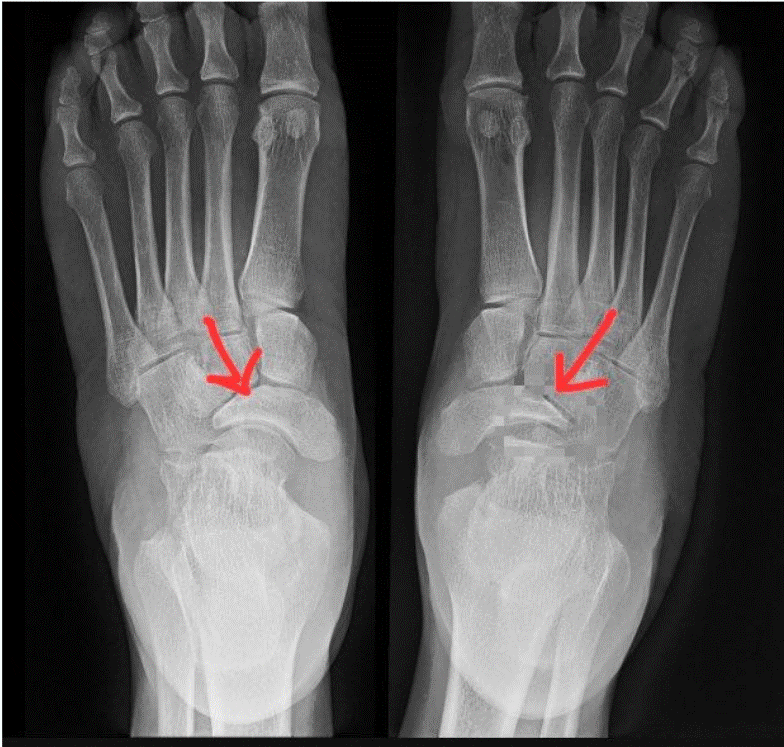

Barefoot running y fractura por estrés: impacto de la presión plantar

El barefoot running, o correr con calzado minimalista, ha ganado popularidad en los últimos años debido a sus supuestos beneficios sobre la técnica de carrera y la prevención de lesiones. Sin embargo, diferentes investigaciones han demostrado que esta práctica puede aumentar la presión plantar en la zona del antepié, elevando así el riesgo de sufrir […]